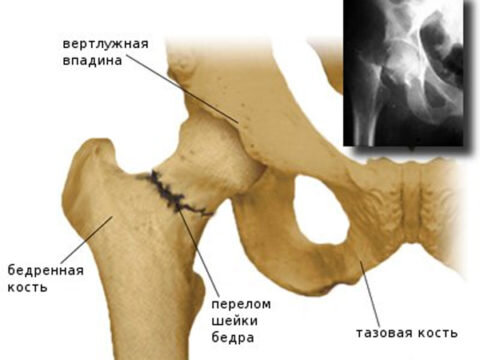

Диагностика и показания к операции

Чтобы определить степень тяжести травмы, подобрать программу лечение и определить в каких направлениях будет проводиться восстановление после перелома тазобедренного сустава, пациенту необходимо пройти осмотр у травматолога и сделать рентгеновский снимок. Даже при отсутствии явных симптомов трещина или полноценный перелом вполне могут присутствовать.

Чтобы оценить степень серьезности полученной травмы необходимо сделать рентгенологические снимки.